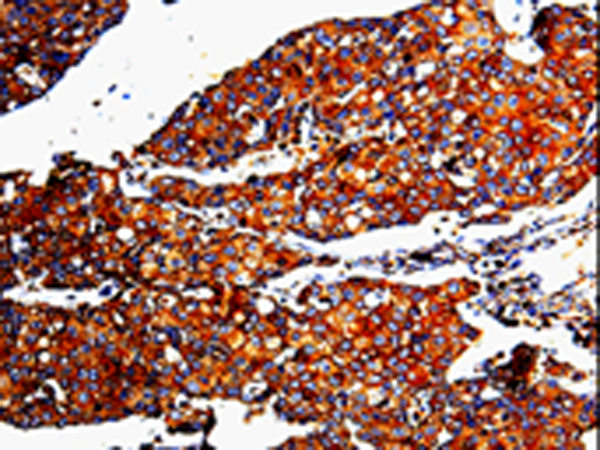

IHC positive control: |

Human breast cancer and Human cervical cancer |

IHC Recommend dilution: |

25-100 |